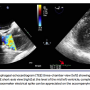

hypertrophy (interventricular septum, 1.3 cm; posterior ventricular wall, 1.5 cm), and severe aortic valve stenosis (aortic valve area, 0.42 cm2; maximum velocity, 5.23 m/s; peak gradient, 109.5 mm Hg; mean gradient, 58.6 mm Hg). There was no intracavitary or LVOT gradient. The patient underwent TAVR using the direct aortic approach through a mini sternotomy. A 29 mm CoreValve Revalving system (Medtronic) was placed at an implant depth of 4 mm. Immediately after full expansion of the new valve frame, the patient developed sinus arrest with slow escape junctional rhythm and underwent temporary right ventricular pacing. Hemodynamic assessment (Figure 1) demonstrated an LV-aortic pressure gradient with the absence of a P-wave on the electrocardiographic tracing. Mid-ventricular cavity obliteration with LVOT flow acceleration was also noted on accompanying transesophageal echocardiogram (Figure 2; Videos 1 and 2). Within 42 seconds, spontaneous restoration of atrial electrical activity occurred with subsequent resolution of the LV-aortic pressure gradient without any medical or procedural intervention (Figure 3; Video 3).